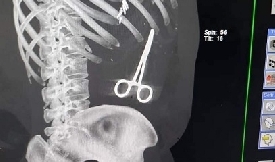

محافظ مأرب يوجه بالتحقيق في فضيحة نسيان " مقص " داخل بطن جريح - وثيقة

أصدر محافظ مأرب سلطان العرادة، اليوم، قراراً بتشكيل لجنة تحقيق ومتابعة في ملابسات ما يثار بخ ...